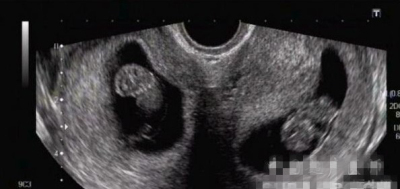

双子宫是双侧副中肾管未完全融合的结果,形成两个分离的宫体和宫颈,附有各自的输卵管、卵巢、圆韧带。双子宫、阴道纵隔、一侧阴道闭锁,常伴泌尿系统异常,多为一侧肾脏发育异常。

患者无任何自觉症状,一般是在人工流产、产前检查甚至分娩时偶然发现。早期人工流产时可能误刮未孕侧子宫,以致漏刮胚胎,子宫继续增大。妊娠晚期胎位异常率增加,分娩时未孕侧子宫可能阻碍胎先露部下降,子宫收缩乏力亦较多见,故剖宫产率增加。异期复孕偶可见于双子宫患者,即不同时期卵子受精后,每侧子宫各有一胎儿。

在几种子宫畸形中,双子宫更容易流产及早产。双角子宫和中隔子宫一般则需手术治疗后才能获取,子宫畸形确诊后,治疗则依其畸形类型,给予不同处理。如单角或双子宫畸形,虽易发生晚期流产或早产,但妊娠本身可促时子宫发育,有50%的活婴率。如纵隔或双角子宫畸形,因宫腔变形、不易受孕,即使妊娠,也易发生流产,应考虑矫形手术。